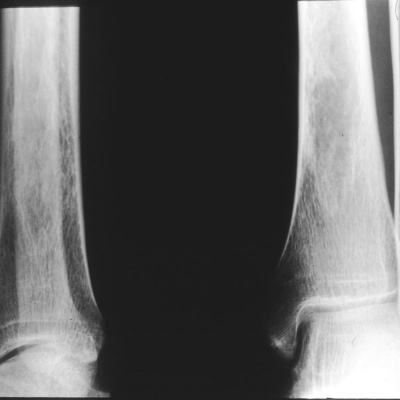

Click to Subscribe to All Ben's Fitness & Get A Free Surprise Gift from Ben. Click here for the full written transcript of this podcast episode In this free October 5, 2009 audio episode special edition recorded from Kona, Hawaii: what you don't know about bone density, recommendations on food combining, healthy saturated fats, whether you burn more calories in hot weather, off-season training tips, how to become a better cyclist and Ben's Ironman 2009 Hawaii Coverage from http://www.everymantri.com (link will open in new window so you don't have to close this one!) . Featured Topic: In today's featured topic, I interview Dr. Carolyn DeMarco. Dr. DeMarco is the author of the The Bone Building Solution - (2006) and the best selling book on women's health, Take Charge of Your Body, Women's Health Advisor (Well Women Press, revised 1997). Recommended by women's groups across the country, this book is the gold standard for women's health information. Her 2nd book is a mini-encyclopedia on natural remedies, D